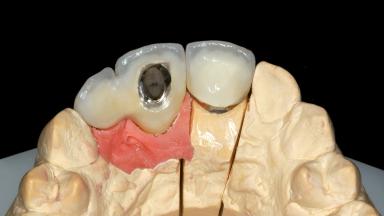

Replacement of an Upper Right Central and Lateral Incisor with an Implant-Supported Crown and a Distal Cantilever

| Abutment Type | Customized |

| Prosthesis Type | FDP |